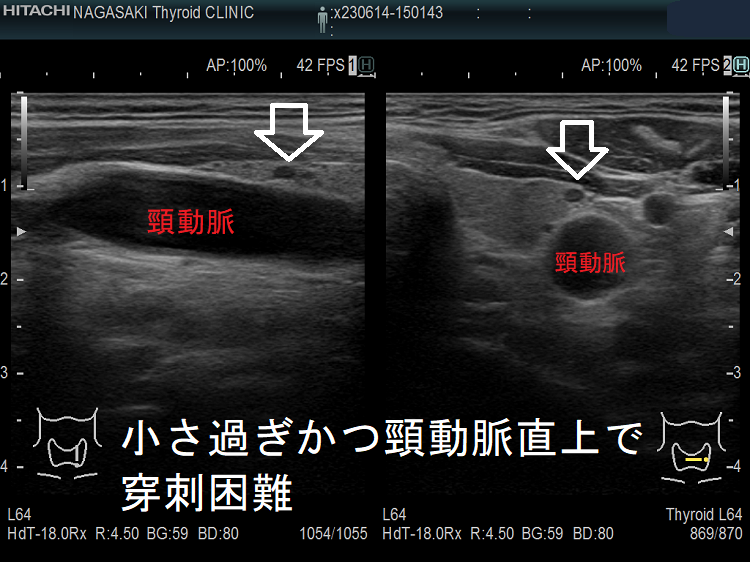

- 頚動脈に接する小さな甲状腺腫瘍

- 頚動脈近傍で、頸動脈に連鎖して拍動する小さな甲状腺腫瘍

甲状腺乳頭癌の可能性があるため、穿刺細胞診したくても、頚動脈や気管を刺してしまう危険を考えれば断念するのが正しいと思います。「退く勇気」も大切なのです。その代わり、甲状腺腫瘍が大きくならないか、腫瘍マーカーは上昇しないか、定期的に経過を見る必要があります。